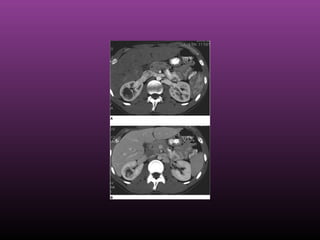

 Renal cell carcinoma. Dedicated renal CT scan obtained before contrastRenal cell carcinoma. Dedicated renal CT scan obtained before contrast

enhancement. Right kidney has an attenuation measurement of 45.7 HUenhancement. Right kidney has an attenuation measurement of 45.7 HU

Renal Cell CarcinomaRenal Cell Carcinoma

 Renal cell carcinoma. Contrast-enhanced dedicated renal CT scan with anRenal cell carcinoma. Contrast-enhanced dedicated renal CT scan with an

attenuation measurement of 101.7 HUattenuation measurement of 101.7 HU